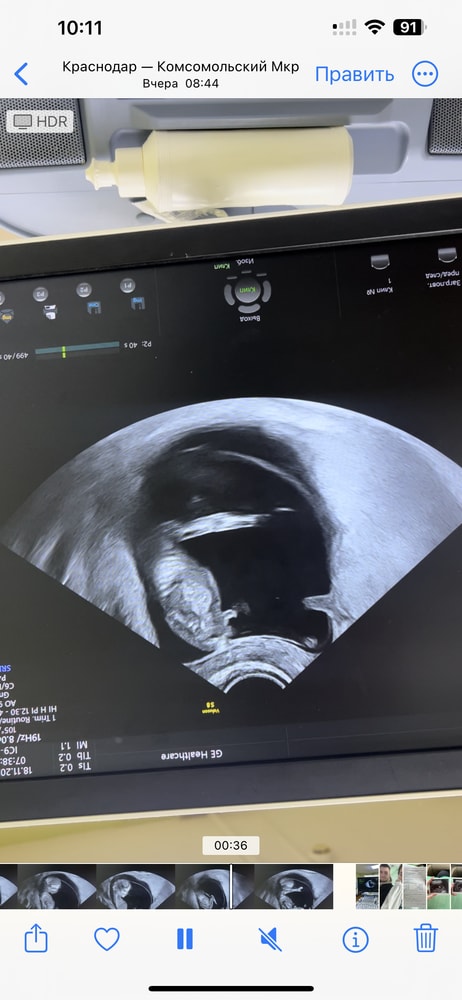

Была на скрининге, сказали пол но врач так сказала «я уверенна, но вот предположительно» и не знаю что пока думать, понятно что пойду еще платно на узи посмотреть

но вот может есть знатоки, и по таким фоткам могут определить)

есть еще скрины с видео, это то что думаю, точно мальчик?)